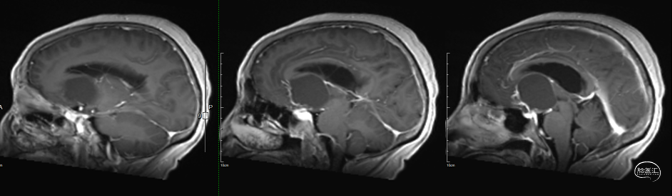

术前影像学资料

术前激素/电解质水平:术前皮质醇、性激素、促肾上腺皮质激素等垂体相关激素,电解质均未见明显异常。

术前诊断:1. 颅咽管瘤 2. 梗阻性脑积水

手术入路选择:患者病灶以囊性为主,病灶完全位于鞍上,病灶靠前,向前上方推挤,病灶主体位于中线。结合病灶实性及起源部位,以及病灶的性质,虽然经鼻具有视角广可直视,对于重要结构干扰较小的优势,常用于鞍内或鞍内-鞍上型;但是此病例主体位于鞍上,起源于垂体柄上部,开颅经额底纵裂入路能直视游离下丘脑边界,同时肿瘤上极未达到三脑室的穹顶,此入路可全切肿瘤,因此,选择开颅经额底纵裂入路。